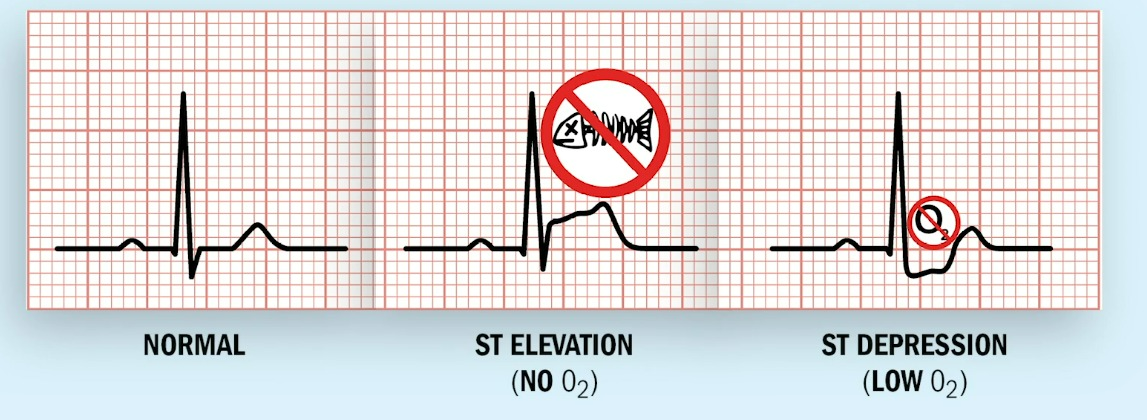

✔️MI 진단 : ECG상 ST elevation